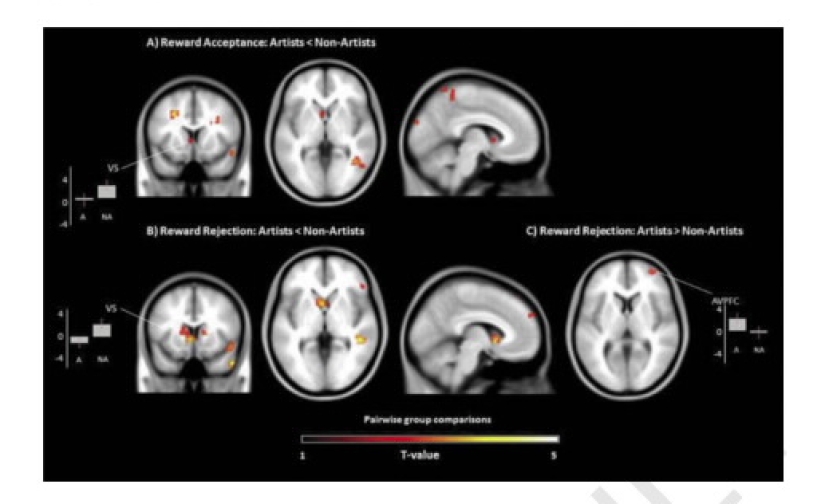

Y aquí está el resultado. La gente creativa, viendo verde, traer el dinero, se mostraron de muy baja actividad en el área de la raya cuerpo — esta área del cerebro responsable de las recompensas. Si los artistas visto libre del color, la máquina de grabado de alta actividad en la corteza prefrontal — esta división es responsable de la producción de dopamina, los cuales, a su vez, provoca una sensación de satisfacción.

Conclusión: la creatividad de la gente no piensa acerca de las recompensas, son importantes sólo en el propio proceso que trae placer. Y resultó que el trabajo independiente es mucho mejor, si saben que no les da dinero.